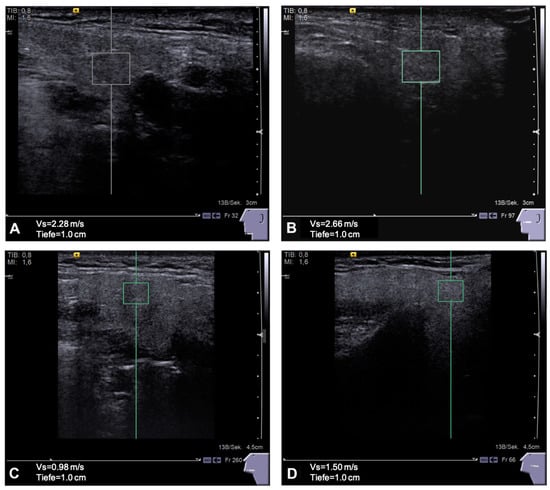

As depicted in Figure 1, the SWV in the ipsilateral PG was higher (2.31 ± 0.74 m/s) compared to the contralateral gland (2.2 ± 0.65 m/s), both being significantly higher compared to the PG of HC (1.87 ± 0.7 m/s, p < 0.001). The ipsilateral SMG had higher SWV (2.23 ± 0.67 m/s) compared to the contralateral gland (2.18 ± 0.54 m/s), both being significantly stiffer than the SMG of the HC group (1.81 ± 0.36 m/s, p < 0.05). To illustrate the glandular images taken to survey the pSWE values, see Figure 2.

Figure 2. Point shear wave elastography (pSWE) images and corresponding shear wave velocities of a patients (A) GSM 2.28 m/s and (B) PG 2.66 m/s are shown. Glands are notably smaller and more fibrous after surgery and adjuvant C/RT. The respective healthy glands and values of a control person are shown in (C) GSM 0.98 m/s and (D) PG 1.50 m/s.